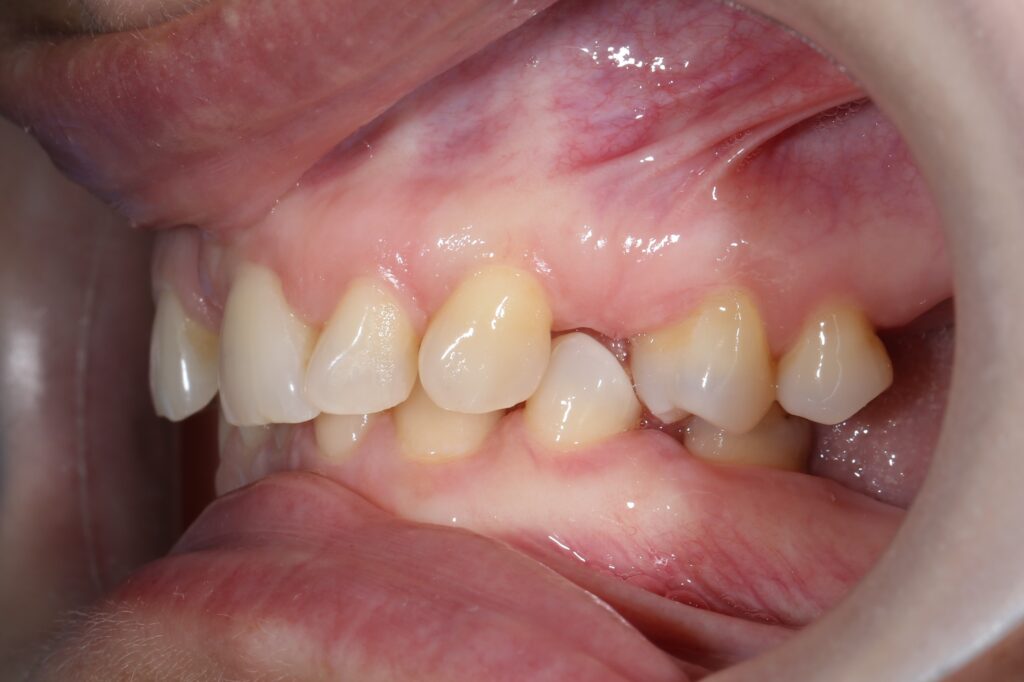

Ситуация до лечения

Из-за множественных давних удалений жевательных зубов, произошла деформация зубных рядов, зубы разъехались в область удаленных, что затрудняло протезирование в момент обращения к ортопеду.

Так же можно отметить сильное снижение высоты прикуса (верхние зубы на 100% перекрывали нижние, что вызывало хроническую травму десны), а также повышенную стираемость твердых тканей зубов, что является следствием повышенной нагрузки, которую много лет испытывали передние зубы, в связи с отсутствием жевательных зубов.